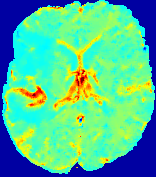

Figure 4: PIANO feature maps for another patient in the ISLES 2017 training set, where the lesion is located in the right hemisphere. Top row: segmented stroke lesion region (white) on different slices. The corresponding slices for the PIANO feature maps are shown in the following rows.

For a better insight into an estimated velocity field 𝐕𝐕{\bf{V}} and diffusion field 𝐃𝐃{\bf{D}}, we compute the following maps: (1) 𝐕rgbsubscript𝐕𝑟𝑔𝑏{\bf{V}}_{rgb}: Color-coded orientation map of 𝐕=(Vx,Vy,Vz)T𝐕superscriptsuperscript𝑉𝑥superscript𝑉𝑦superscript𝑉𝑧𝑇{\bf{V}}=(V^{x},V^{y},V^{z})^{T}, obtained by normalizing 𝐕𝐕{\bf{V}} to unit length and mapping its 3 components to red, green, blue respectively; (2) 𝐕2subscriptnorm𝐕2\|{\bf{V}}\|_{2}: 222 norm of 𝐕𝐕{\bf{V}}; (3) D𝐷D: scalar field in Eq. 5.

Fig. 3 and Fig. 4 show the PIANO feature maps estimated from two ISLES 2017 patients: all are highly consistent with the lesion in both cases. Details of the blood flow trajectories are revealed in 𝐕rgbsubscript𝐕𝑟𝑔𝑏{\bf{V}}_{rgb} by the ridged patterns and the sharp changes of colors in the unaffected (right) hemisphere, while the flat patterns appearing within the lesion provide little directional information about the velocity and indicate low velocity magnitudes. Velocity magnitudes are more directly visualized via 𝐕2subscriptnorm𝐕2\|{\bf{V}}\|_{2}, from which one can easily locate the lesion where 𝐕2subscriptnorm𝐕2\|{\bf{V}}\|_{2} is low. D𝐷D also indicates lower diffusion values in the lesion, though with less contrast potentially due to the fact that it captures the accumulated effect of CA diffusion at the voxel-level.